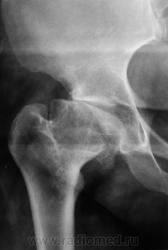

Это не асептический некроз, его уже давно нет, а состояние после перенесенного ранее правостороннего асептического некроза головки правого бедра, с грибовидной остаточной ее деформацией, и наружным, едва заметным, подвывихом. Перелома впадины не видно...

5-я стадия, с укорочением правой нижней конечности. Готовится на эндопротезирование?

На эндопротезирование не готовится, не хочет. "Функционально" чувствует себя хорошо, ведет активный образ жизни, просто, наступило время для очередного переосвидетельствования с желанием сохранить имеющуюся группу.